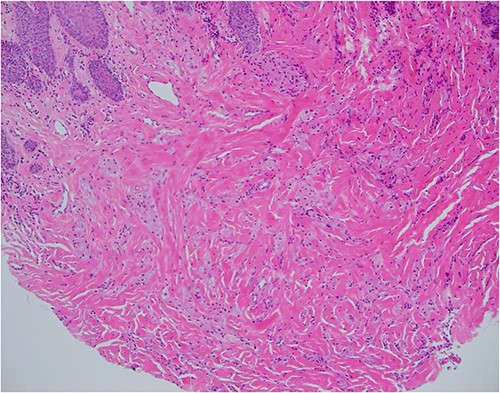

Haematoxylin and eosin stain, 40× magnification, showing reactive epithelial hyperplasia on the surface, this can be mistaken for squamous cell carcinoma in a superficial biopsy.